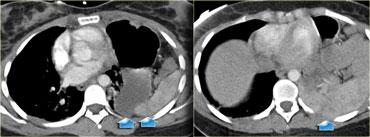

Bên trái là hình ảnh của một bệnh nhân có tổn thương bên phải.

Trên phim X-quang ngực, hình ảnh trông như thể chỉ đơn thuần là nâng cao vòm hoành hoặc có thể có tràn dịch màng phổi dưới phổi.

Cũng có thể đây là liệt cơ hoành từ trước.

Bây giờ hãy tiếp tục với các hình ảnh CT.

Hãy mô tả các dấu hiệu bên trái rồi tiếp tục.

Hình ảnh axial cho thấy vùng mờ trên phim X-quang ngực thực chất chính là gan.

Khi theo dõi đường bờ của gan, có hình dạng bất thường (mũi tên vàng).

Có sự gián đoạn của trụ cơ hoành, đây là dấu hiệu không đặc hiệu (mũi tên xanh nhỏ).

Trên hình axial, có hình ảnh lõm vào mặt sau của gan do máu trong lồng ngực.

Trên tái tạo MPR mặt phẳng sagittal, hình ảnh lõm vào của gan và ‘dấu hiệu cổ thắt’ được thể hiện rõ ràng.